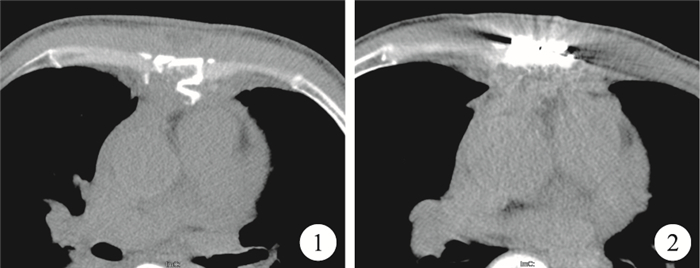

患者,男,59歲。因胸部金屬鈍器撞擊傷7 d入院。查體見生命體征平穩,輕度貧血貌,胸骨右緣第3肋間見一長約2 cm皮膚挫裂傷,胸骨中段可捫及骨擦感。雙肺呼吸音清晰,心音清晰。血紅蛋白(HB)92 g/L,丙氨酸氨基轉氨酶(ALT)1 020 U/L,門冬氨酸氨基轉氨酶(AST)1 016 U/L。胸骨CT三維成像掃描提示胸骨體中段粉碎性骨折,部分骨片向后突入縱隔內(圖 1),心包受累可能,雙側胸腔少量積液。坐位心包腔彩色多普勒檢查提示少量心包積液。上腹部CT提示肝臟右后葉密度稍降低,肝周少量積液可能。入院后給予胸帶固定胸廓、鎮痛、加強呼吸道管理及保肝等治療。監測HB無進行性下降,但心包及胸腔積液逐漸增多,術前(受傷第17 d)復查心臟超聲提示心包及右側胸腔大量積液,行心包穿刺抽出暗紅色不凝血約350 ml,右側胸腔閉式引流管引流出暗紅色不凝血約700 ml。術中經胸骨正中切口,用電鋸分別由胸骨上下兩端向胸骨斷端靠近,在胸骨骨折區域用剪刀仔細分離,切開胸骨后探查見:胸骨中段粉碎性骨折,其后板斷端嵌入心包內,壓迫右心室流出道,局部心包欠完整;心包內見陳舊血性積液及血凝塊共約300 ml。清除積血后可見右心室流出道表面局部挫傷及滲血。徹底止血,游離碎裂骨片并取出,置心包、右側胸腔引流管,間斷縫合關閉心包。胸骨斷端用鋼絲2根縱向固定后,取鎳鈦記憶合金胸骨環抱器固定于胸骨骨折處。術后患者恢復順利,復查胸部X線片、胸骨CT三維成像、心臟、腹部彩色超聲均無異常(圖 2)。